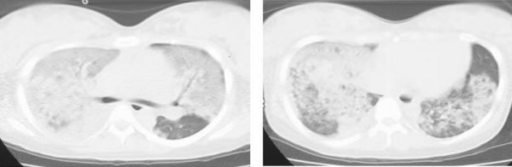

Chest computed tomography of a patient revealing severe hypoxia due to amniotic fluid embolism: a case report. Imanaka H, Takahara B, Yamaguchi H, Nakataki E, Mano A, Inui D, Oto J, Nishimura M - Journal of medical case reports (2010)

| actual | 12:42 25 nov 2021 | 512 × 167 (61 kB) | Rossdonaldson1 (discusión | contribs.) | Chest computed tomography of a patient revealing severe hypoxia due to amniotic fluid embolism: a case report. Imanaka H, Takahara B, Yamaguchi H, Nakataki E, Mano A, Inui D, Oto J, Nishimura M - Journal of medical case reports (2010) |